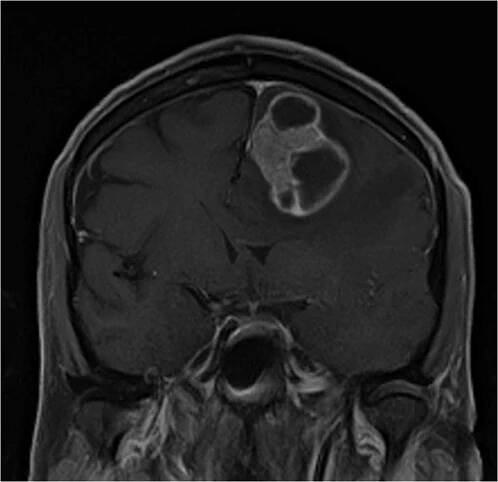

Chirurgická léčba mozkových metastáz

Funkční anatomie a neurologické projevy mozkových metastáz

Mozkové metastázy jsou častou komplikací systémových nádorových onemocnění, z nichž 60–75 % se v průběhu života stává symptomatickými.